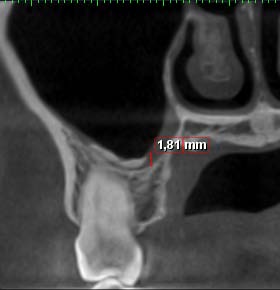

? Thickening of Schneider's membrane: The measurement was performed between the point where the mucous thickening was maximal and the sinus floor. ? Sinus ventilation: has been evaluated by the freedom of the ostium of the maxillary sinus. ? Polyp and cyst: were determined by the presence of homogeneous, mono or poly-geodic sinus opacity with a regular contour. ? Oro-antral communication (OAC): has been determined by the sinus membrane perforation. ? Presence or not of an inflammatory process of dental origin: was determined by the presence or not of a peri-apical lesion.

Several theories are put forward. First, the ventilation of the maxillary sinus would be responsible. The ventilation of the maxillary sinus via its ostium is essential to maintain its biological balance. It was found decreased in 78% of the cases in our work. Mucus in the sinus plays a major role as a protective colloid so that the salts do not concentrate. (36) However, once the inflammation is established, sinus ventilation is impaired, sinus drainage is compromised, mucous secretions accumulate, increase PH, change the mineral environment and lead to the precipitation of calcium salts which would lead to the formation of intra-sinus calcifications. (29) Second, the formation of idiopathic calcifications of endogenous origin is linked to the osteogenic power of the Schneider membrane. Srouji et al. analyzed the osteogenic potential of the human maxillary sinus Schneider membrane using in vitro and in vivo assays. (37) Samples of the membrane were used to prepare cell cultures for histological studies. The results showed that the cells derived from these membrane extracts grow in culture and express markers of osteoprogenitor cells (alkaline phosphatase, protein 2 specific to bone morphogenesis, osteopontin, osteonectin and osteocalcin). Mineral deposits have also been found including phosphate and calcium ions. Once differentiated, these membrane-derived cells were transplanted in vivo. Therefore, histological evidence of osteogenesis has been found at the site of transplantation. The results of this study showed the presence of osteoprogenitor cells at the Schneider membrane and asserted its osteogenic potential. However, the precise location of these osteoprogenitor cells among the layers constituting the Schneider membrane was not determined. The authors have referred to the richly vascularized chorion but also to the connective tissue similar to the periosteum next to the maxillary bone. The osteogenic potential of the Schneider membrane has been approved by several authors and in several studies. (38,39) It would explain the significant success of dental implants (93.5%) placed in the atrophied maxillary posterior region; With a residual bone of 5 mm to 9 mm: these implants are placed "in a tent pole" without using bone substitutes but only by providing space for the blood clot (40). This technique eliminates the high cost of bone substitutes but also reduces the risk of post-operative complications related to bone grafting (41). Indeed Schneider's membrane plays the role of framework for the multiplication of bone cells and their maturation (42). More studies are needed to be able to predict bone formation by focusing on the individual potential of each patient. (40) The thickness of the sinus mucosa was measured in several studies. In the present study, thickening of the sinus mucosa was reported when the thickness of the mucosa was greater than 1 mm. (FIG. 6). Its prevalence was 88.9%. Other studies have reported a prevalence ranging from 48.4% to 66% (2.8). This difference may indicate that the presence of intrasinus calcification is a contributing factor to the thickening of the sinus mucosa. It should be noted, however, that athickening of the sinus mucosa is not necessarily a sign of pathology. Allergic reactions and smoking are factors correlated with an increase in the thickness of the sinus mucosa. (43) Antral polyps are the most common benign pathologies of the maxillary sinus. Their prevalence varies between 1. 4% and 25% (2,8). Our study found a prevalence of 44%. This high frequency would indicate a relationship between the presence of antral polyps and intra-sinus calcifications.